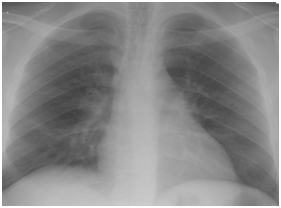

Figure 4C Follow up Chest X-ray three days after starting oseltamivir therapy.

Figure 4D Follow up chest X-ray after 7 days from starting H1N1 therapy.

Figure 4 H1N1 radiological pictures in a diabetic 28-year-old transplant recipient.